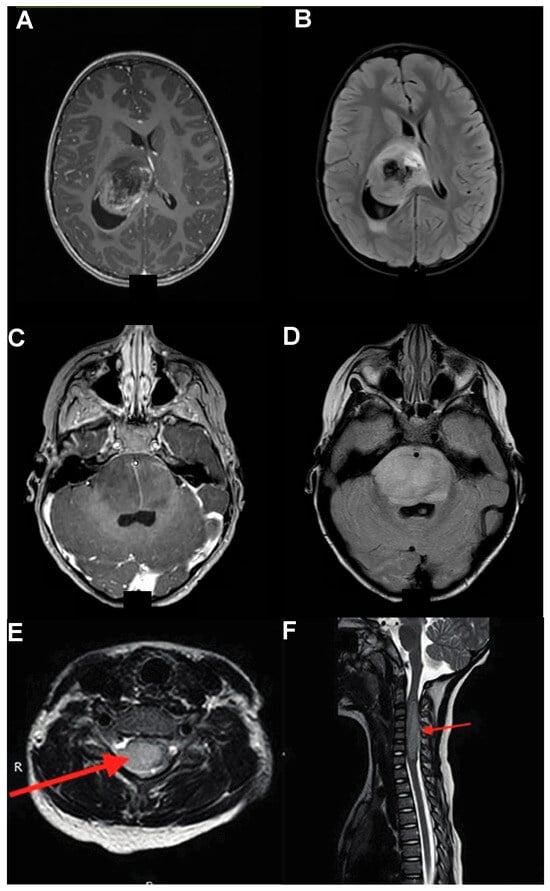

Spinal DMGs share features with their cranial counterparts, with growth patterns logically restricted by the limited axial spread possible within the spinal cord; thus, these lesions have a predominant rostro-caudal elongation rather than anterior–posterior or medio-lateral one. They are characterized by a significant FLAIR signal often spanning multiple spinal levels and poorly differentiated contrast enhancement (Figure 2E,F) [,]. Spinal DMGs can be difficult to distinguish from other astrocytic spinal lesions; these tend to be more eccentric and can have stronger contrast enhancement, albeit the two entities can be difficult to separate by MRI alone [].

Figure 2.

DMGs Imaging Characteristics. (A,B) Thalamic gliomas show involvement of various thalamic nuclei (A) and a significant FLAIR signal (B) causing locoregional mass effect, ventricular entrapment, and internal capsule involvement. (C,D) DIPG and midbrain DMGs are characterized by wispy heterogeneous contrast enhancement (C) and enlargement of the pons (D). (E,F) Spinal gliomas, like their cranial counterparts, are characterized by heterogenous contrast enhancement (E), with significant cranio-caudal spread (F). Adapted from [].